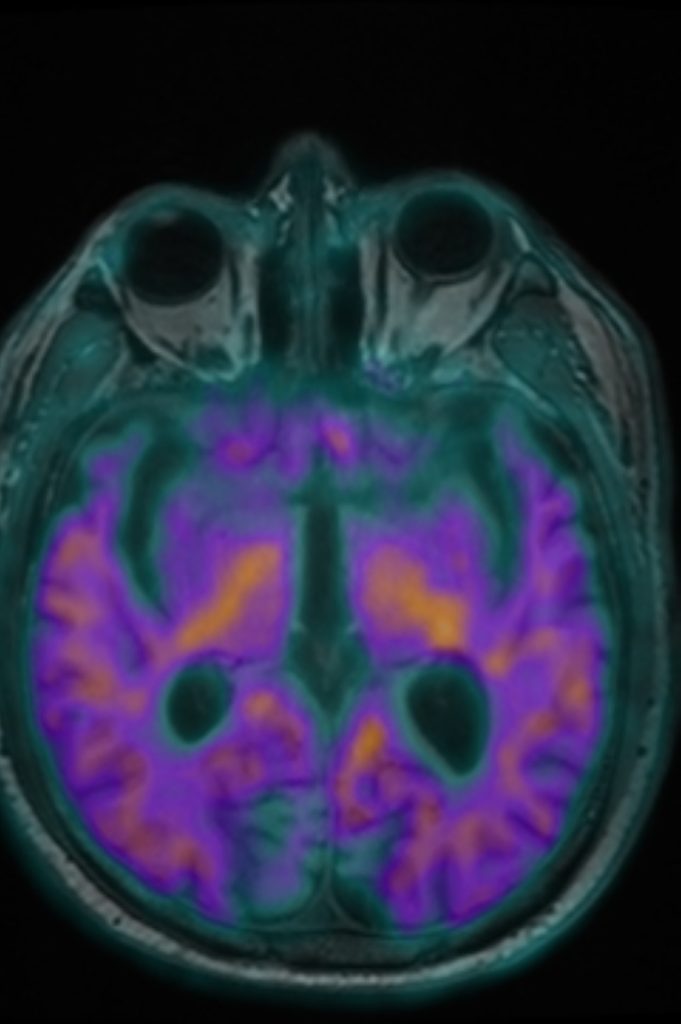

دشن مركز التصوير الجزيئي I-One، التابع لشركة وادي جدة، الذراع الاستثماري لجامعة الملك عبدالعزيز، اليوم الاثنين 15 ديسمبر 2024م، خدمة التصوير الجزيئي Amyloid PET MRI لتشخيص مرض الزهايمر، وذلك بالتعاون مع شركة Oryx Isotopes لإنتاج وتوريد مادة Amyloid (18F – FBB).

ويأتي هذا الإنجاز ضمن أعمال مركز التصوير الجزيئي I-One، الذي يعد الأول والوحيد من نوعه على مستوى المنطقة الغربية والجنوبية بالمملكة في إنتاج المستحضرات الصيدلانية المشعة باستخدام المسارع الذري (Cyclotron)، وتقديم خدمات التصوير البوزيتروني المقطعي PET/CT، والتصوير البوزيتروني الطبقي المدمج بالرنين المغناطيسي PET/MRI، وهو الجهاز الأول والوحيد من نوعه على مستوى المملكة.

بهذا التدشين، أصبح مركز التصوير الجزيئي I-One الأول والوحيد على مستوى الشرق الأوسط الذي يقدم خدمة تشخيص مرض الزهايمر باستخدام تقنية PET/MRI، مما يعزز مكانته الرائدة في مجال التصوير الجزيئي على المستويين المحلي والإقليمي.